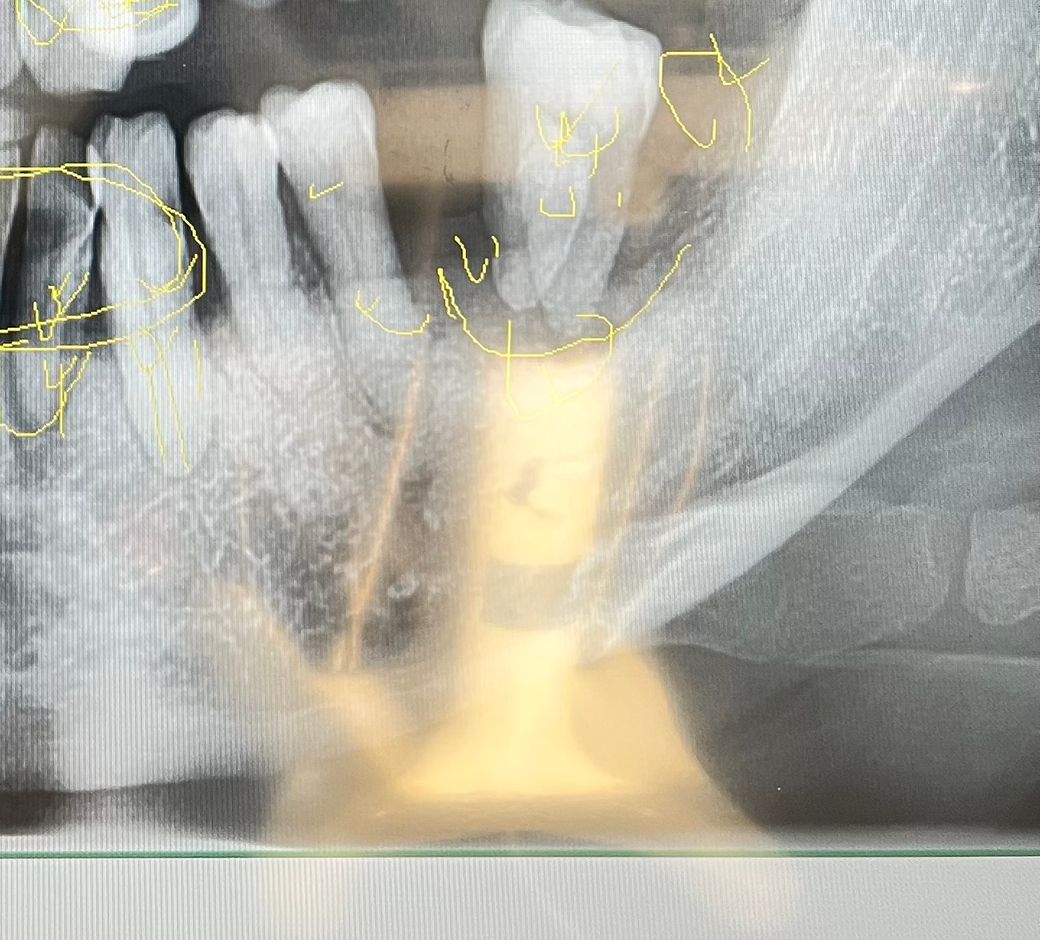

이게 맞다면 7번이 예전에 먼저 빠졌고 6번이 조금씩 이동하면서 7번자리쪽으로 좀 가있는 상태거든요

궁금한게 치과 선생님들은 이 사진만 보고 6번인지 7번인지 아실 수 있나요?

6번자리에 하나만 임플란트 하기로 했는데 보험금 청구할때 치아 위치가 중요해서 이걸 7번인줄 알고 7번 발치로 기록하실까봐 이걸 병원에 제가 얘기를 해야하는지 궁금합니다

2. 과거에 7번 발치 후, 6번이 저렇게 뒤로 이동했다고 표현하셨는데 교정력이 가해진 것도 아닌데 치아가 저렇게 이동하는 건 현실적으로 드문일이지 싶습니다. 발치 전 처음 파노라마 사진이 있다면 좋을 것 같은데요. 애초에 6번 결손에 7,8번만 있다가 8번을 뺀게 아닐까 싶기도 하고요.

4. 어쨌든 지금 상황으로선 치주상태가 안 좋아 저 치아도 빼야하고, 저 치아의 치식에 따라 발치 후 임플란트의 보험 적용 여부가 갈리기 때문에 그게 질문자분한테 중요한 부분이네요.

5. 일반적으로 보험 임플란트의 경우 동일 치식 적용이 가장 깔끔한데 골자는 기능회복입니다. 즉, 지금 남아있는 '기능을 못하는 ' 어금니를 빼고 기능회복을 위해 6번자리에 임플란트를 심는다고하면 보험 적용될 가능성이 높습니다. 그러니까 정리하자면 저 어금니를 빼고 안빼고는 내지는 발치 치식이 6번이든 7번이든 보험 임플란트 적용에는 문제가 없지 싶습니다. 애초에 6번 자리에 있어야 하는 어금니가 없고 기능을 못하는 상태니까요.